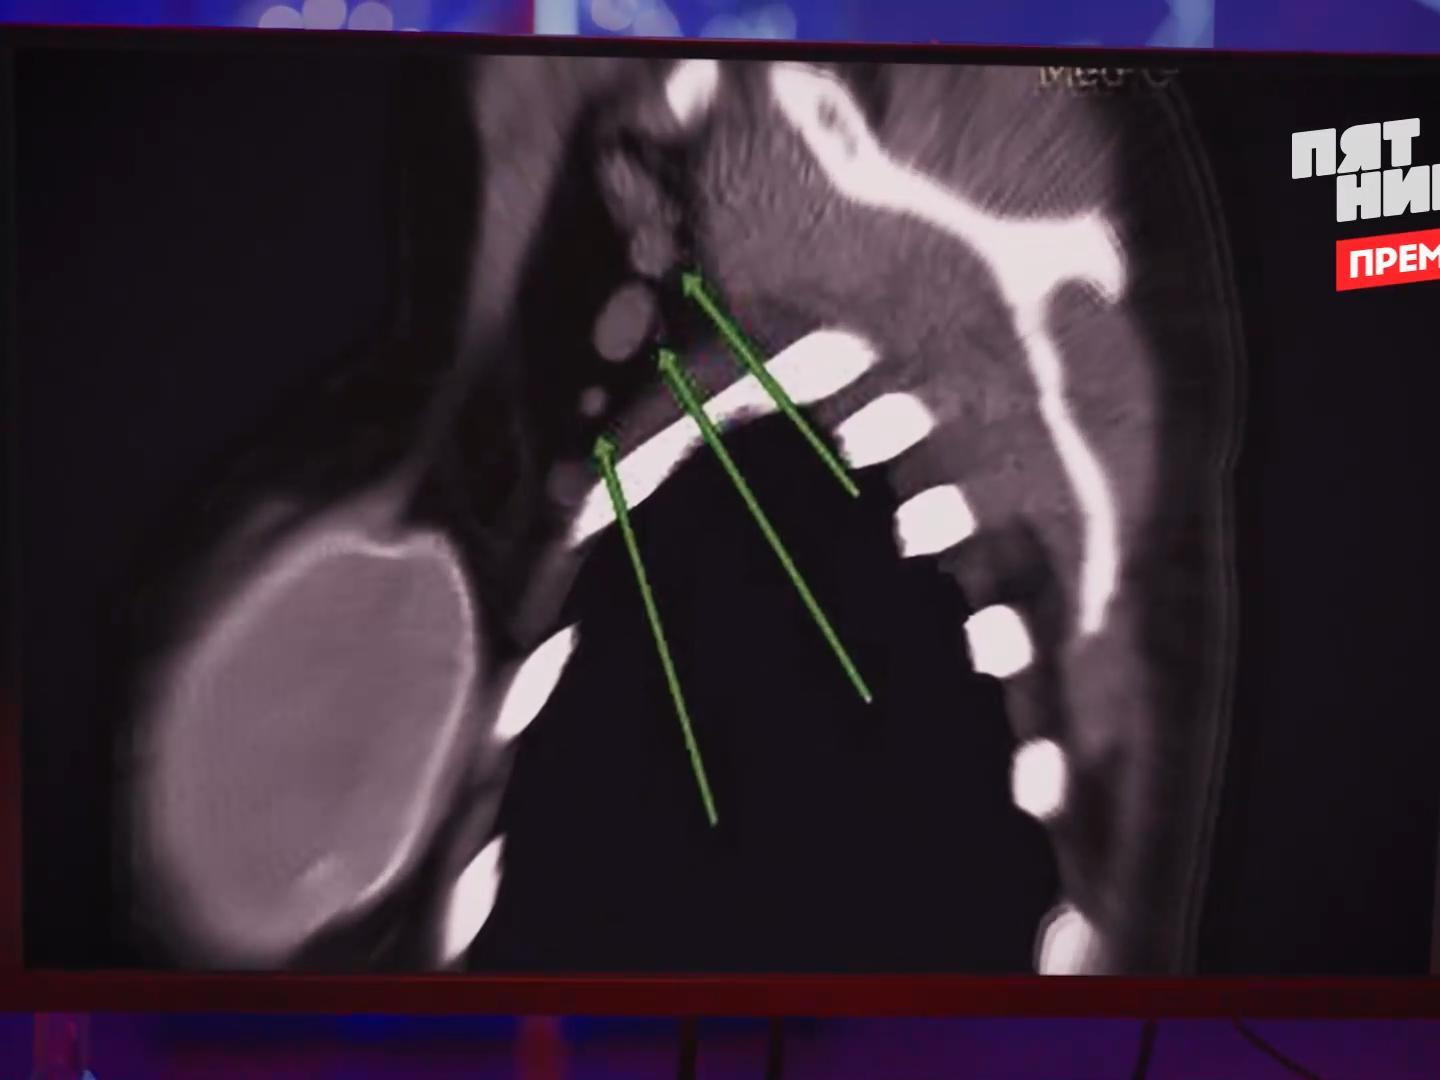

An ultrasound revealed that Inna«s implant had burst, allowing silicone to migrate throughout her body.

Silicone entry caused inflammation in a lymph node.

In the conclusion, the doctors indicated: «silicone in the lymph nodes.» This is a very rare case of complications.